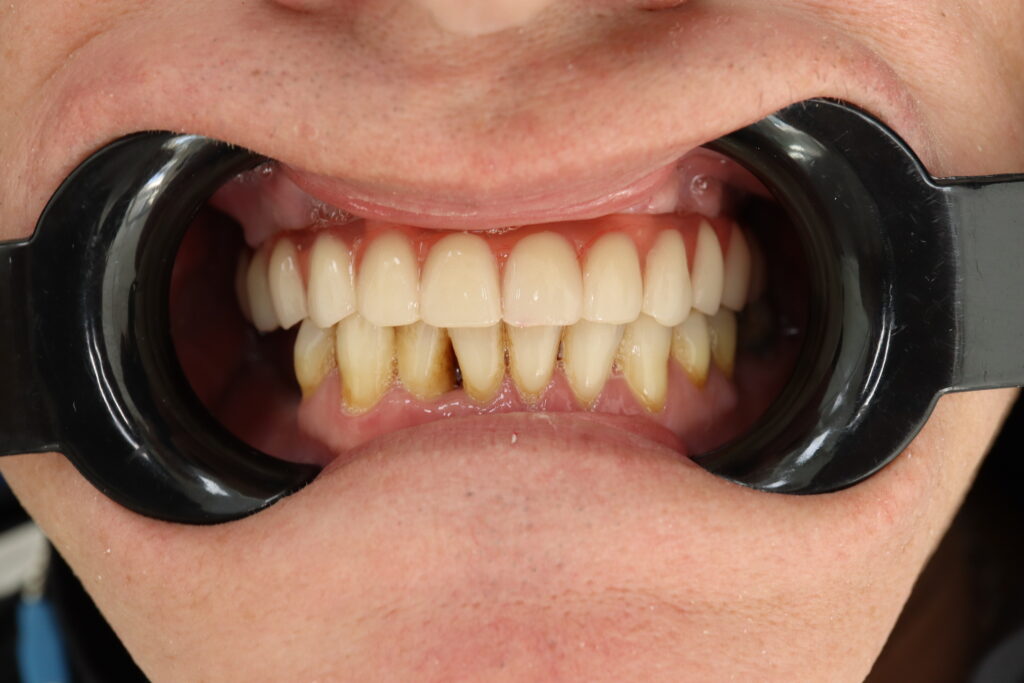

Результат

После консультации было принято решение об удалении зубов на верхней челюсти, которые находились в неудовлетворительном состоянии

и проведении комплексной имплантации по системе All-on-4.

результат протезирования